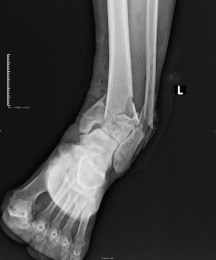

DR全称为数字化X线摄影,就是老百姓口中的平片。是日常大家接触较多的一项检查,它是利用X线的穿透能力成像,检查时就像给身体内部拍了一张平面影像的照片,由于被照物体密度的不均匀,拍摄之后的底片上会形成黑白不一的颜色,所以我们经常能看出片子上骨头的位置颜色偏白色,软组织则显像不清。

优点:适用人群较广,成像速度快,且价格相对较便宜,便于临床重症、急症患者的诊治。

缺点:DR受制于身体组织影响,影像可能会存在重叠和隐藏的情况,有时需要多次或多角度拍摄才能看清。

DR成像也容易受衣物、首饰甚至过厚的软组织影响,所以一般作为初步检查使用。